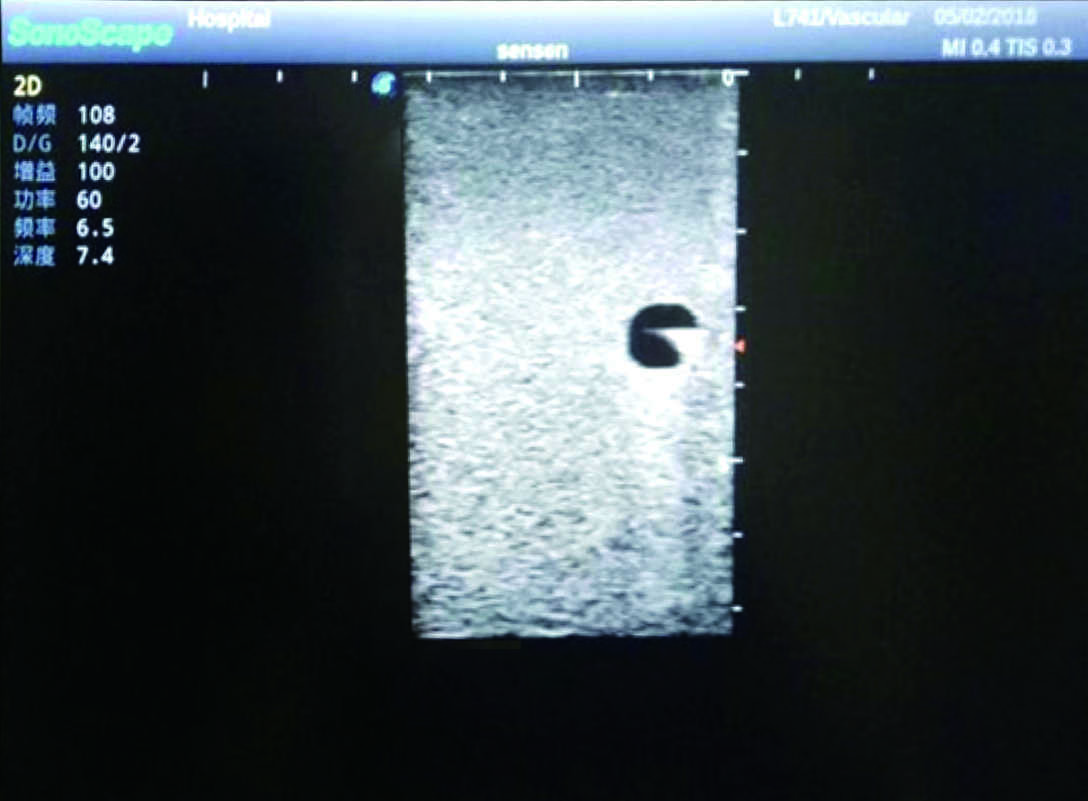

2) It can be used by real ultrasound machines

3) Clear and real images of the tissues and organs (basilic vein and superior vena cava)

6) Detect whether the catheter is properly placed